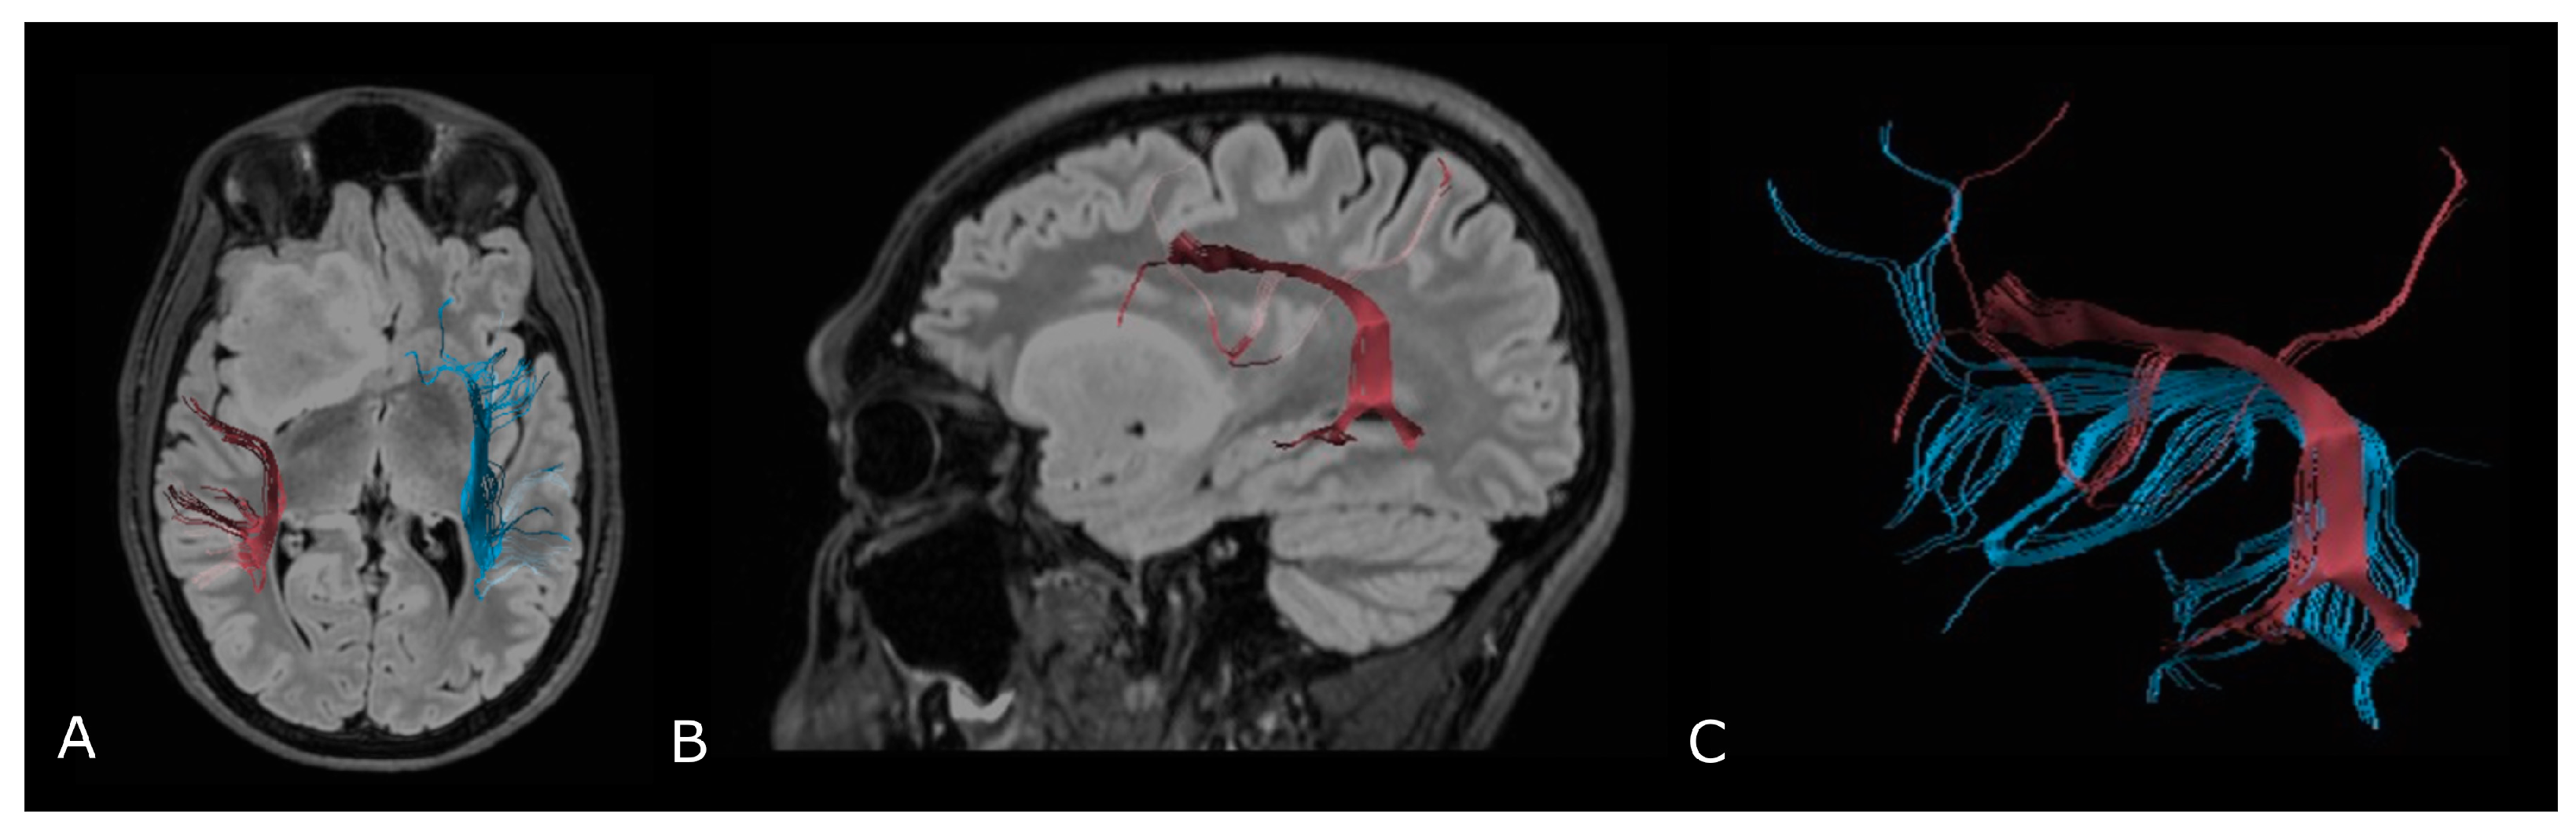

Figure 7.

Tractographic reconstruction of arcuate fasciculi. DTI of the direct pathway of both arcuate fasciculi (AF) fused with anatomic axial (A); and sagittal (B) FLAIR images. The right AF on the affected side is superiorly and posteriorly displaced by an IDH-mut frontal-temporal-insular astrocytoma; (C) 3D rendering of both arcuate fasciculi.